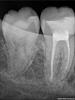

nes84 Опубликовано 30 августа, 2010 Поделиться Опубликовано 30 августа, 2010 здравствуйте, уважаемые стоматологи! я девушка, мне 25 лет, проблемы с десневым карманом 6-ки ( или 7-ки...).сначала думала, что у меня так болит зуб. боль была очень сильная, отдавала в челюсть и язык.сходила к доктору, оказалось это из-за воспаления десневого кармана. карман почистили и промыли. план лечения простой: полоскать Ротоканом, смазывать метрогилом. после заживления ставить коронку тем самым закрыв щель между зубами и сохранив зуб. также возможно придется убрать "нависающую" часть пломбы.доктору доверяю, но зуб болит, характер боли изменился. теперь на холодное реагируют соседние зубы.что делать? ждать? очень страдаю.... Ссылка на комментарий

DokDent Опубликовано 31 августа, 2010 Поделиться Опубликовано 31 августа, 2010 здравствуйте, уважаемые стоматологи! я девушка, мне 25 лет, проблемы с десневым карманом 6-ки ( или 7-ки...).сначала думала, что у меня так болит зуб. боль была очень сильная, отдавала в челюсть и язык.сходила к доктору, оказалось это из-за воспаления десневого кармана. карман почистили и промыли. план лечения простой: полоскать Ротоканом, смазывать метрогилом. после заживления ставить коронку тем самым закрыв щель между зубами и сохранив зуб. также возможно придется убрать "нависающую" часть пломбы.доктору доверяю, но зуб болит, характер боли изменился. теперь на холодное реагируют соседние зубы.что делать? ждать? очень страдаю.... А зачем ждать?Обратитесь к своему доктору,он снимет реакцию зубов на температурные раздражители,обработает Ваш "карман" и сделает всё,что необходимо.Если мало помогает метрогил,попробуйте Холисал-гель.Ошибка многих пациентов в том,что они сидят и ждут " с моря погоды",в надежде,что всё само собой образуется,хотя Ваш доктор может быстро избавить Вас от мучений.Не болейте! Ссылка на комментарий